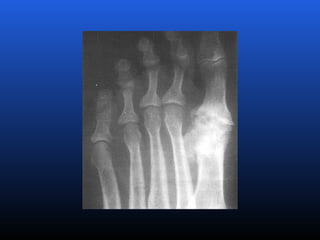

RADIOLOGIA

No início da doença não se observam anormalidades.

Com seu desenvolvimento, observam-se:

 Diminuição do espaço intra-articular

 Esclerose subcondral (eburnação)

 Osteófitos;

 Erosão e anquilose óssea (pseudocistos ósseos).

RADIOLOGIA No início dadoença não se observam anormalidades. Com seu desenvolvimento, observam-se:  Diminuição do espaço intra-articular  Esclerose subcondral (eburnação)  Osteófitos;  Erosão e anquilose óssea (pseudocistos ósseos).